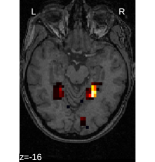

For fMRI brain decoding, we use a standard visual-object recognition dataset [2]. We perform on all 5 subjects intra-subject 2-class decoding of 14 pairs of stimuli of varying difficulties (listed on Figure 1). To measure prediction accuracy, we perform cross-validation, leaving out 2 of the 12 sessions.

Finally, an important aspect of the brain decoders is whether they segment well the brain regions that support the decoding. Such a question is hard to validate, yet there is evidence that TV- is a good approach [5]. Fig. 2 displays the decoder maps for the object-recognition tasks. For these tasks, we expect prediction to be driven by the functional areas of the visual cortex [27]. Indeed, the maps outline regions in known visual areas. The graph-net maps are much more scattered and less structured than the others. Conversely, the social sparsity maps are sparser and outline a smaller number of clusters.